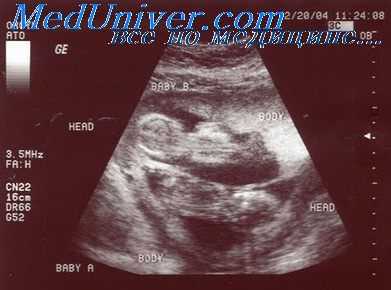

От 1 до 2% всех родов составляют роды после многоплодия, которые обусловливают от 10 до 14% всей перинатальной заболеваемости, что в 5-10 раз превышает таковую при одноплодных беременностях. Вследствие более широкого применения вспомогательных репродуктивных технологий число беременностей с наличием одного и более плодов резко увеличилось за последние 20 лет. Целью ранней диагностики многоплодной беременности и связанных с ней осложнений является снижение показателей перинатальной заболеваемости и смертности.

Эхография позволяет определить зиготность и число хориальных и амниотических оболочек, а также описать расположение плаценты, предлежание плодов и диагностировать такие осложнения в течении беременности, как диссоциация развития плодов, наличие патологических сосудистых анастомозов, дисбаланс объема околоплодных вод в разных плодовместилищах и формирование коллизии (спутывания) пуповин.